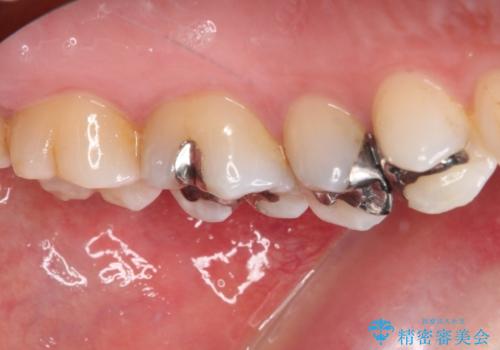

- 銀歯をセラミックにしたいとのことで来院された患者様です。

まず麻酔をして銀歯を外し、むし歯を除去し、形を整えて型取りします。

それを左右に分けて行いました。